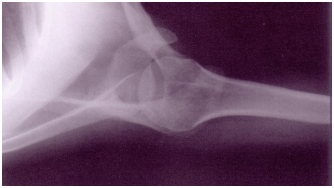

Observe:

A figura acima corresponde a uma incidência de

A

perfil de escápula.

B

ombro oblíqua.

C

ombro axial.

D

ombro AP.